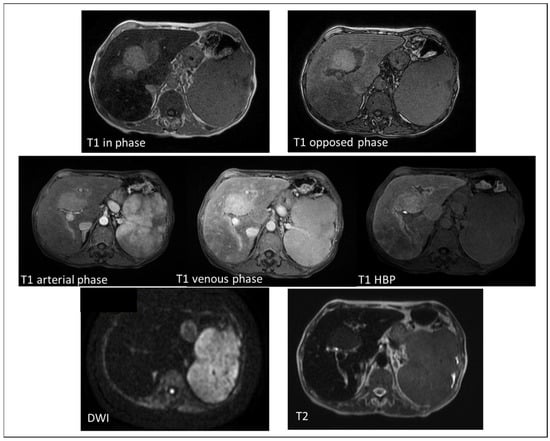

4.1. Hepatocellular Carcinoma